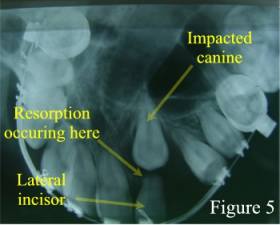

Impacted Canine Resorbing Lateral Incisor

Also, be aware that wisdom teeth aren’t the only teeth that can become impacted. Other teeth in the mouth can also become impacted and cause dental disease (figure 5). These teeth will require extraction as well.